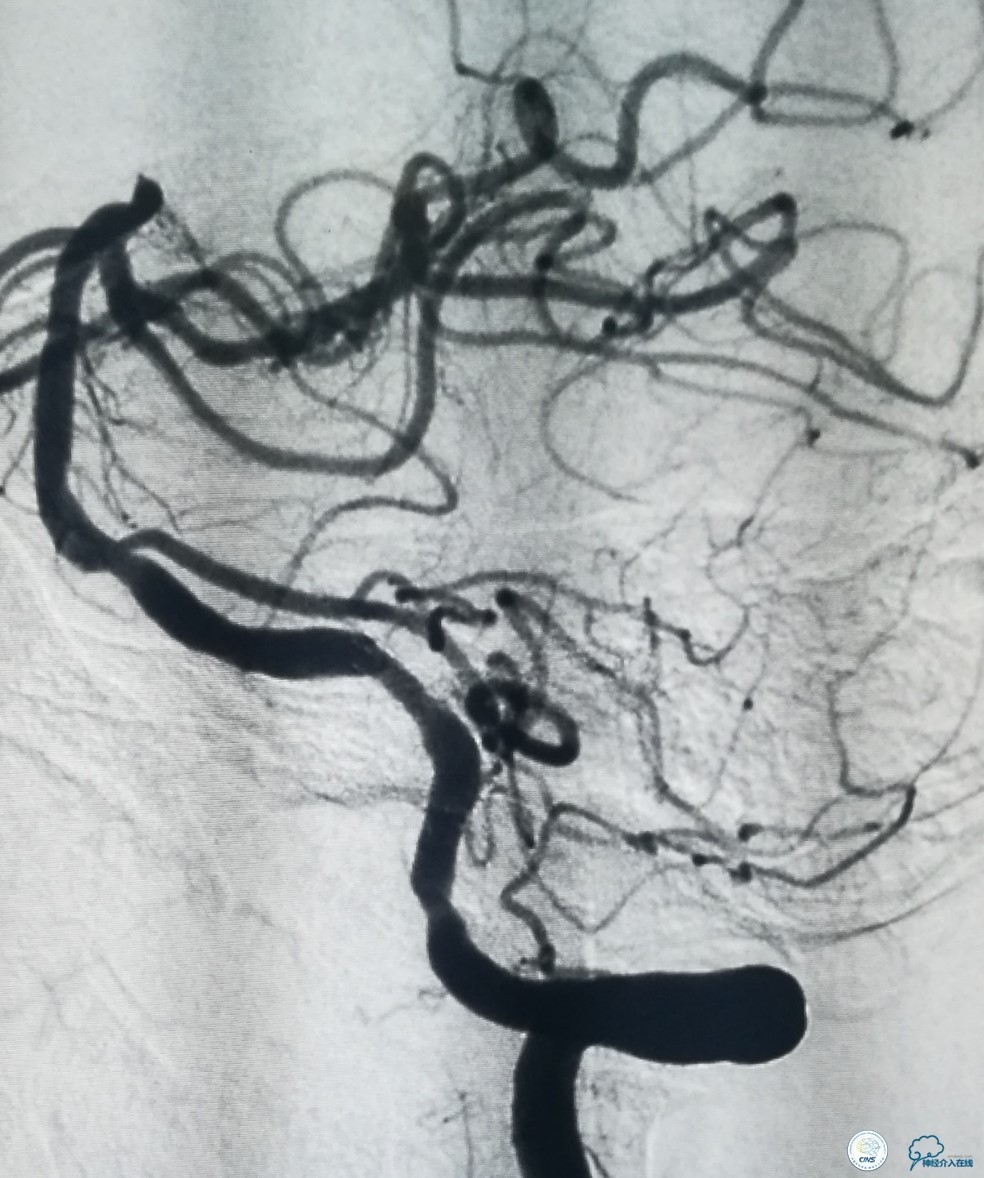

遂撤出Navien导管,将长鞘置于左椎动脉开口部,Traxcess(0.014″200cm)微导丝+Echelon-10微导管结合将微导管置于左大脑后动脉P2段,交换Transend(0.014″300cm)微导丝至左大脑后动脉P2段,Gateway球囊(2.25mm×15mm)狭窄段预扩张(图9)。

图9

其后放置Wingspan支架(3.5 mm× 15mm),释放后造影见支架贴壁良好,远端血管显影好,前向血流TICI3级(图10)。

图10